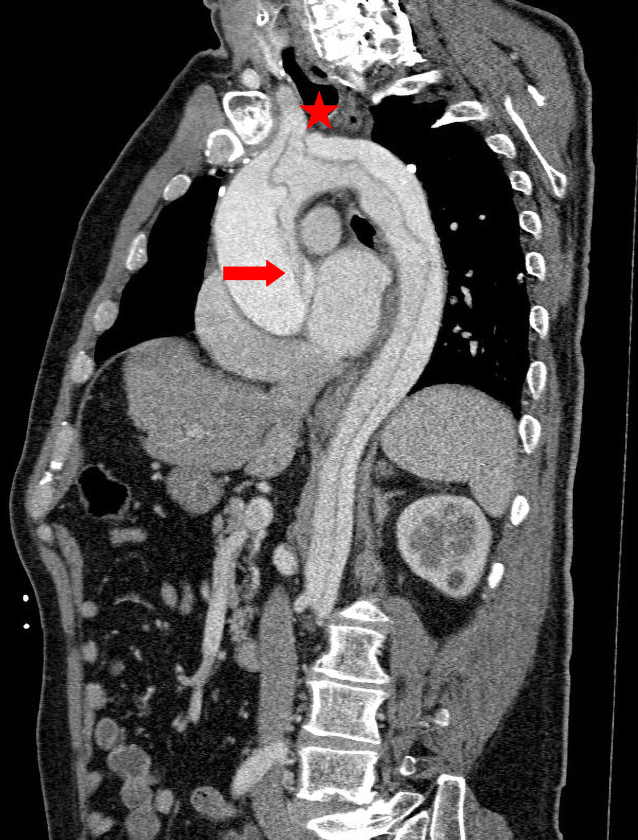

Der Beginn der Dissektion lag auf Höhe des Aortenbulbus (Abb. 2). Die Dissektion dehnte sich bis in die Iliakalgefäße aus (Abb. 3). Die Koronarien und die distalen hirnversorgenden Gefäße waren regelrecht kontrastiert. Zudem ergab sich kein Anhalt auf eine Endorganischämie oder ein Hämatoperikard. Aus ärztlicher Sicht ergab sich eine klare Indikation zur sofortigen operativen Versorgung.

Abb. 2

Sagittalschnitt: „Entry“ der Dissektion auf Höhe des Aortenbulbus (Pfeil), Beteiligung der Kopf-/Halsgefäße (Stern) und Verlauf bis weit in die Aorta abdominalis

Bild vergrößern